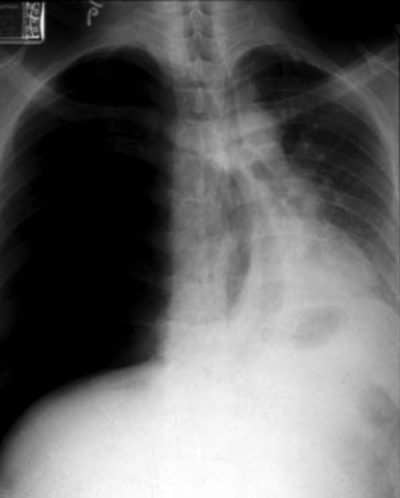

Paciente vítima de trauma torácico com clinica de MV diminuidos ou abolidos, macicez a percussão e jugular colabada, evoluindo com choque hipovolêmico…

Diagnóstico, conduta…

HEMOTÓRAX

Sangramento de vasos intercostais ou parênquima (geralmente auto-limitado)

Conduta: Toracostomia (drenagem em selo d’água)

Avaliar débito de sangue

Quando indicar toracotomia no hemotórax?

Se hemotórax maciço